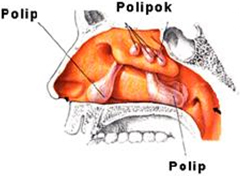

Az orrpolip az orr nyálkahártyájának krónikus gyulladás eredményeképpen kialakuló jóindulatú, egyre növekvő duzzanata. Ebben szerepet játszik a levegő fokozott szennyezettsége, az allergiát okozó allergének, az örökletes és helyi faktorok, a tüdőasztma és egyes allergiáért felelős gombafajok. A lakosság mintegy 2%-a szenved ebben a betegségben. A nyálkahártya túlburjánzás beterjed az orrmelléküregekből az orrüregbe, majd folyamatosan növekedve, fokozatosan kitölti azt.

Az orrüregben a levegő áramlásának mechanikus gátoltsága miatt nehezített orrlégzés alakul ki, ennek következtében a szájon át történő légzés kerül előtérbe, ezért az orr nyálkahártya mellett a torok és a garat nyálkahártyája is kiszárad, gyakrabban alakul ki torokgyulladás. A tünetek: teltségérzés az orrban, orrfolyás, orrgarati váladékcsurgás, szájszárazság, fülpanaszok, szaglászavar, horkolás. Ahogyan az orrpolip növekszik, úgy ezek a panaszok is fokozódnak.

| Polipok az orrüregben és az orrmelléküregben. |

A orrpolip lehet egy- vagy kétoldali, kitölthet egy vagy több orrjáratot, az orrbemenetet, és beterjedhet az orrgaratba, a rostasejtekbe és a melléküregekbe is. A polipok elzárják az arcüregek, a homloküreg kivezető nyílásait is a rostasejtekével egyetemben.

Az orrmelléküregekben a nyálkahártya túlburjánzás elzárja a természetes kivezető nyílásokat, emiatt nem tudnak átszellőzni, ezért gyakori a krónikus arcüreggyulladás, szinte folyamatos a színtelen nyákos vagy gennyes orrváladékozás (nátha), a fejfájás, valamint az orrhangú beszéd.